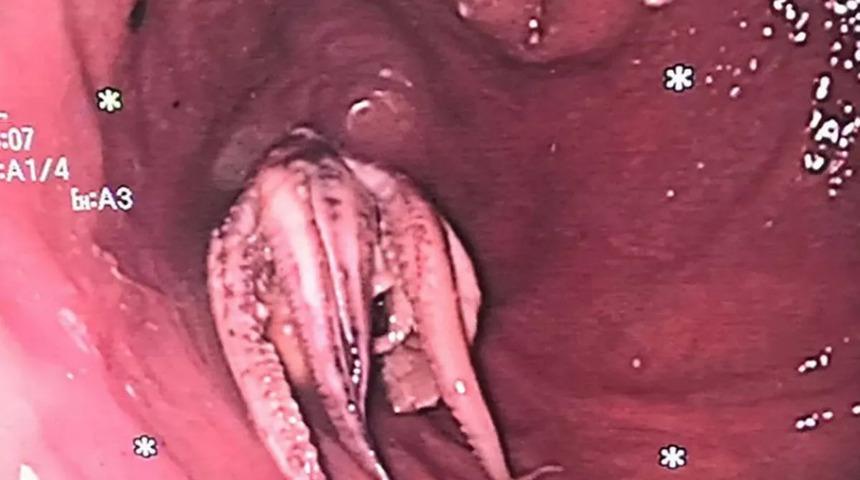

Doktorlar yaptığı inceleme sonrasında adamın yemek borusuna takılan şeyin bir ahtapot olduğunu fark etti.

Vantuzlarıyla birlikte toplamda 5 santimetre büyüklüğünde olduğu tespit edilen ahtapotu çıkarmak için doktorlar adeta seferber oldu.